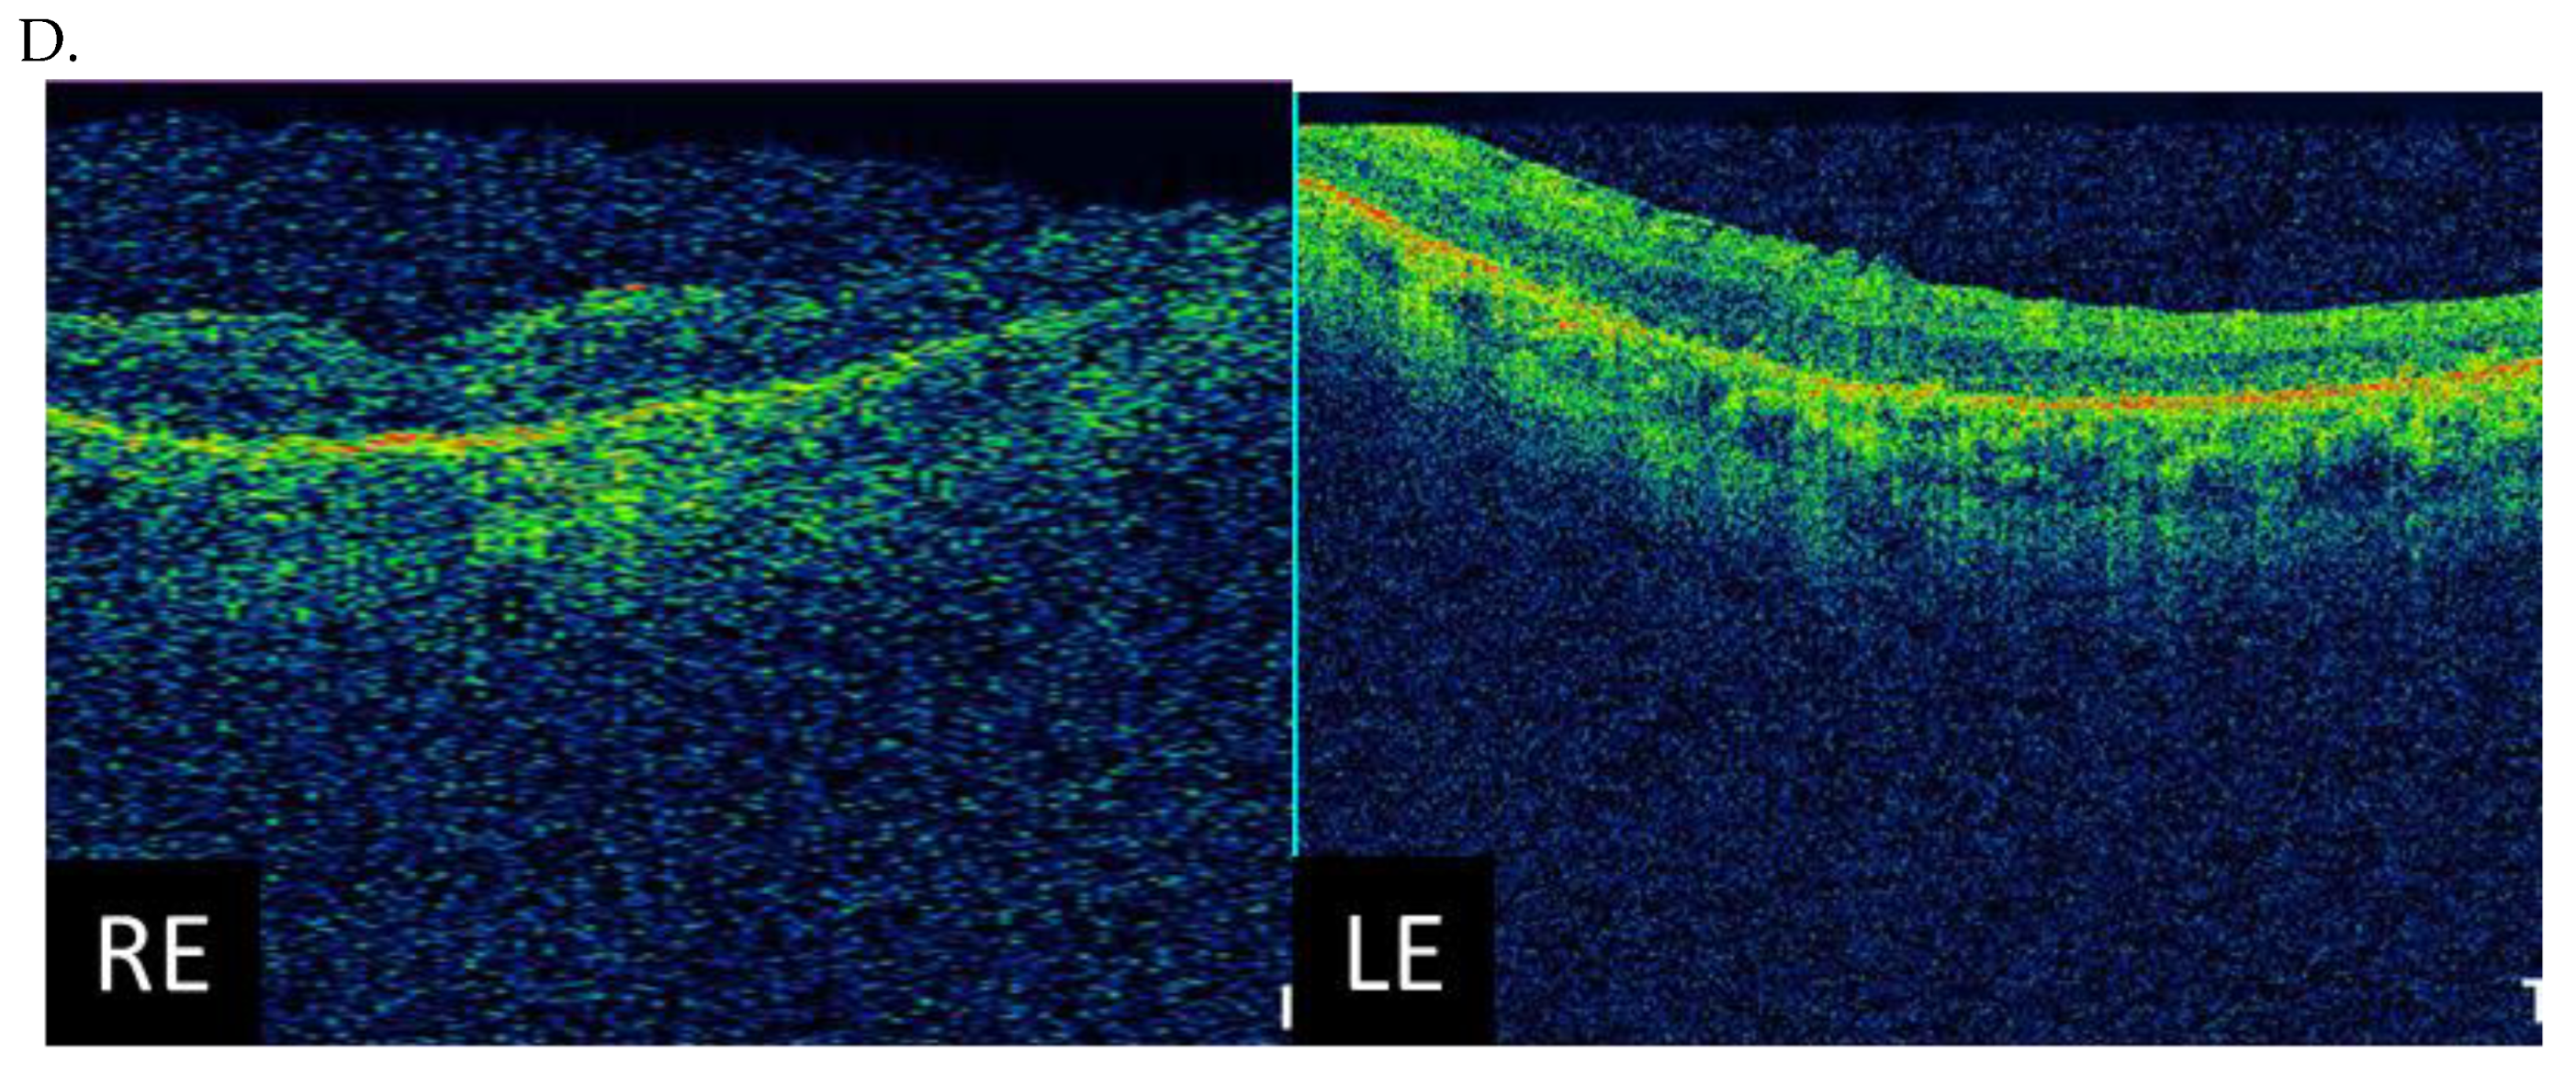

| I (family 1) | c.2442_2445del | 10 | 31 | 0.7 0.7 | Advanced constriction, only V4e remarkable | 277 264 |

| II (family 2) | c.2340_2341del | 12 | 42 | 0.01 0.01 | Advanced constriction, only V4e remarkable | 208 205 |

| III (family 3) | c.2587G>T | 8 | 36 | 0.5 0.6 | Middle constriction, V4e, III4e and I4e remarkable | 143 147 |

| IV (family 4) | c.2389dup | 10 | 22 | 0.7 0.7 | Middle constriction, V4e, III4e remarkable | 223 225 |

| V (family 4) | c.2389dup | 10 | 22 | 0.4 0.2 | Middle constriction, V4e, III4e and I4e remarkable | 260 240 |

| VI (family 5) | c.2455dup | 14 | 25 | 0.6 0.3 | Middle constriction, V4e, remarkable | 205 186 |

| VII (family 6) | c.593G>T | 12 | 20 | 0.5 0.5 | Middle con-striction, V4e, III4e and I4e remarkable | 250 245 |

| VIII (family 7) | c.799G>C | 6 | 47 | 0.2 0.3 | Middle con-striction, V4e, III4e and I4e remarkable | 240 230 |